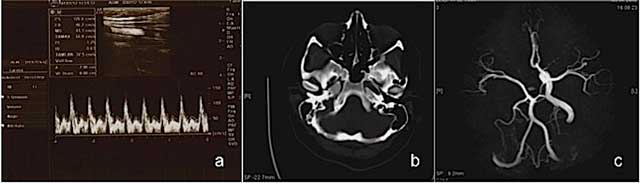

Figure 1

Ultrasound and Color Doppler images reveal right ICA agenesis and externalization flow pattern of right CCA (a); an axial CT image at bone window reveals absent right bony carotid canal (b); MR angiography image shows right ICA agenesis and anomalous origin of ophthalmic artery (c) in Case 1.